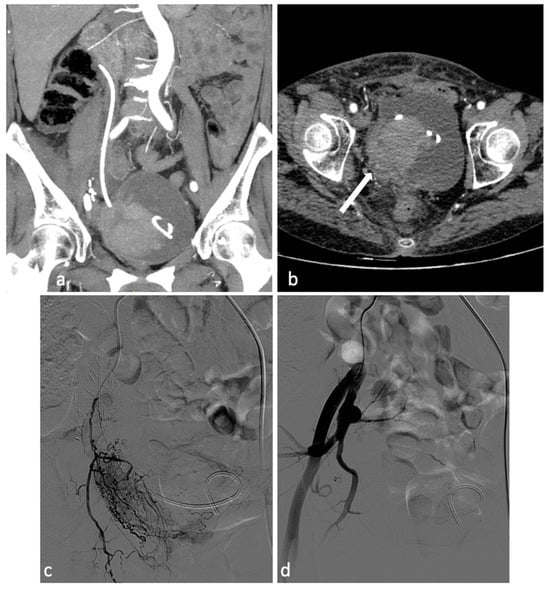

Figure 5.

Pelvic recurrence of endometrial neoplasm causing vaginal bleeding. A 65-year-old patient with endometrial neoplasm treated by total hysterectomy, salpingo-oophorectomy, and right uretero-neocystostomy with DJ catheter placement, presenting with significant vaginal bleeding. CT investigation (a,b) shows a neoplastic mass (4 × 3 cm) in the right pelvis involving the bladder trigone, distal ureter, right bladder dome and vaginal dome. Concomitant intravesical clot measuring at least 6 cm and a clot in the right vaginal dome (b, arrow). Selective catheterization of the right hypogastric artery was performed. Angiography confirmed the presence of a hypervascular pathological formation of the right pelvis, with disorganized arterial hypervascularization (c). After superselective coaxial microcatheterization of the main afferent branch of the lesion, its embolization with PVA particles (350–500 microns) and occlusion with a 2 × 25 mm metal microspiral was performed. Control angiography shows effective devascularization of the lesion (d).